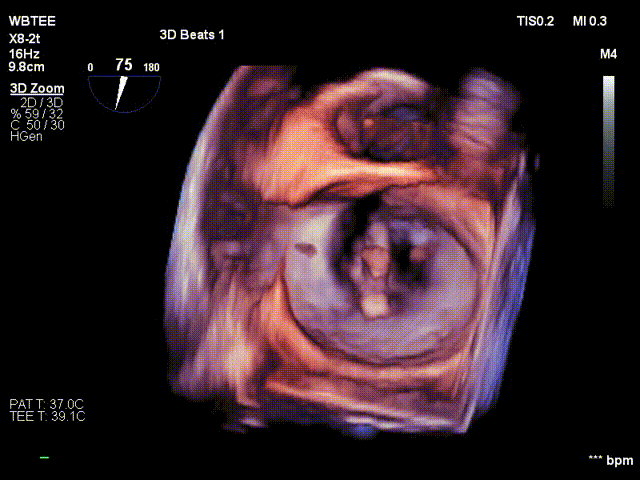

术前行经食道超声评估

原发性二尖瓣反流,反流程度4+;二尖瓣瓣口面积4.15cm²,平均跨瓣压差5mmHg,二尖瓣前叶(A2)长度23.35mm,二尖瓣后叶长度(P2)长度13.2mm;左室射血分数67%。患者手术风险高,操作难度大,经心脏瓣膜团队多次充分讨论评估后,决定行经导管二尖瓣缘对缘修复治疗。

术前MDT策略:从解剖结构来看二尖瓣后叶脱垂伴连枷涉及整个2区,累及3区和1区,宽度15mm左右,且连枷高度甩起高度有7-8mm,可见长达10.4mm的飘样回声,术前策略预计使用两个二尖瓣夹,较小的二尖瓣口面积和较高平均跨瓣压差,是一次高难度的挑战。